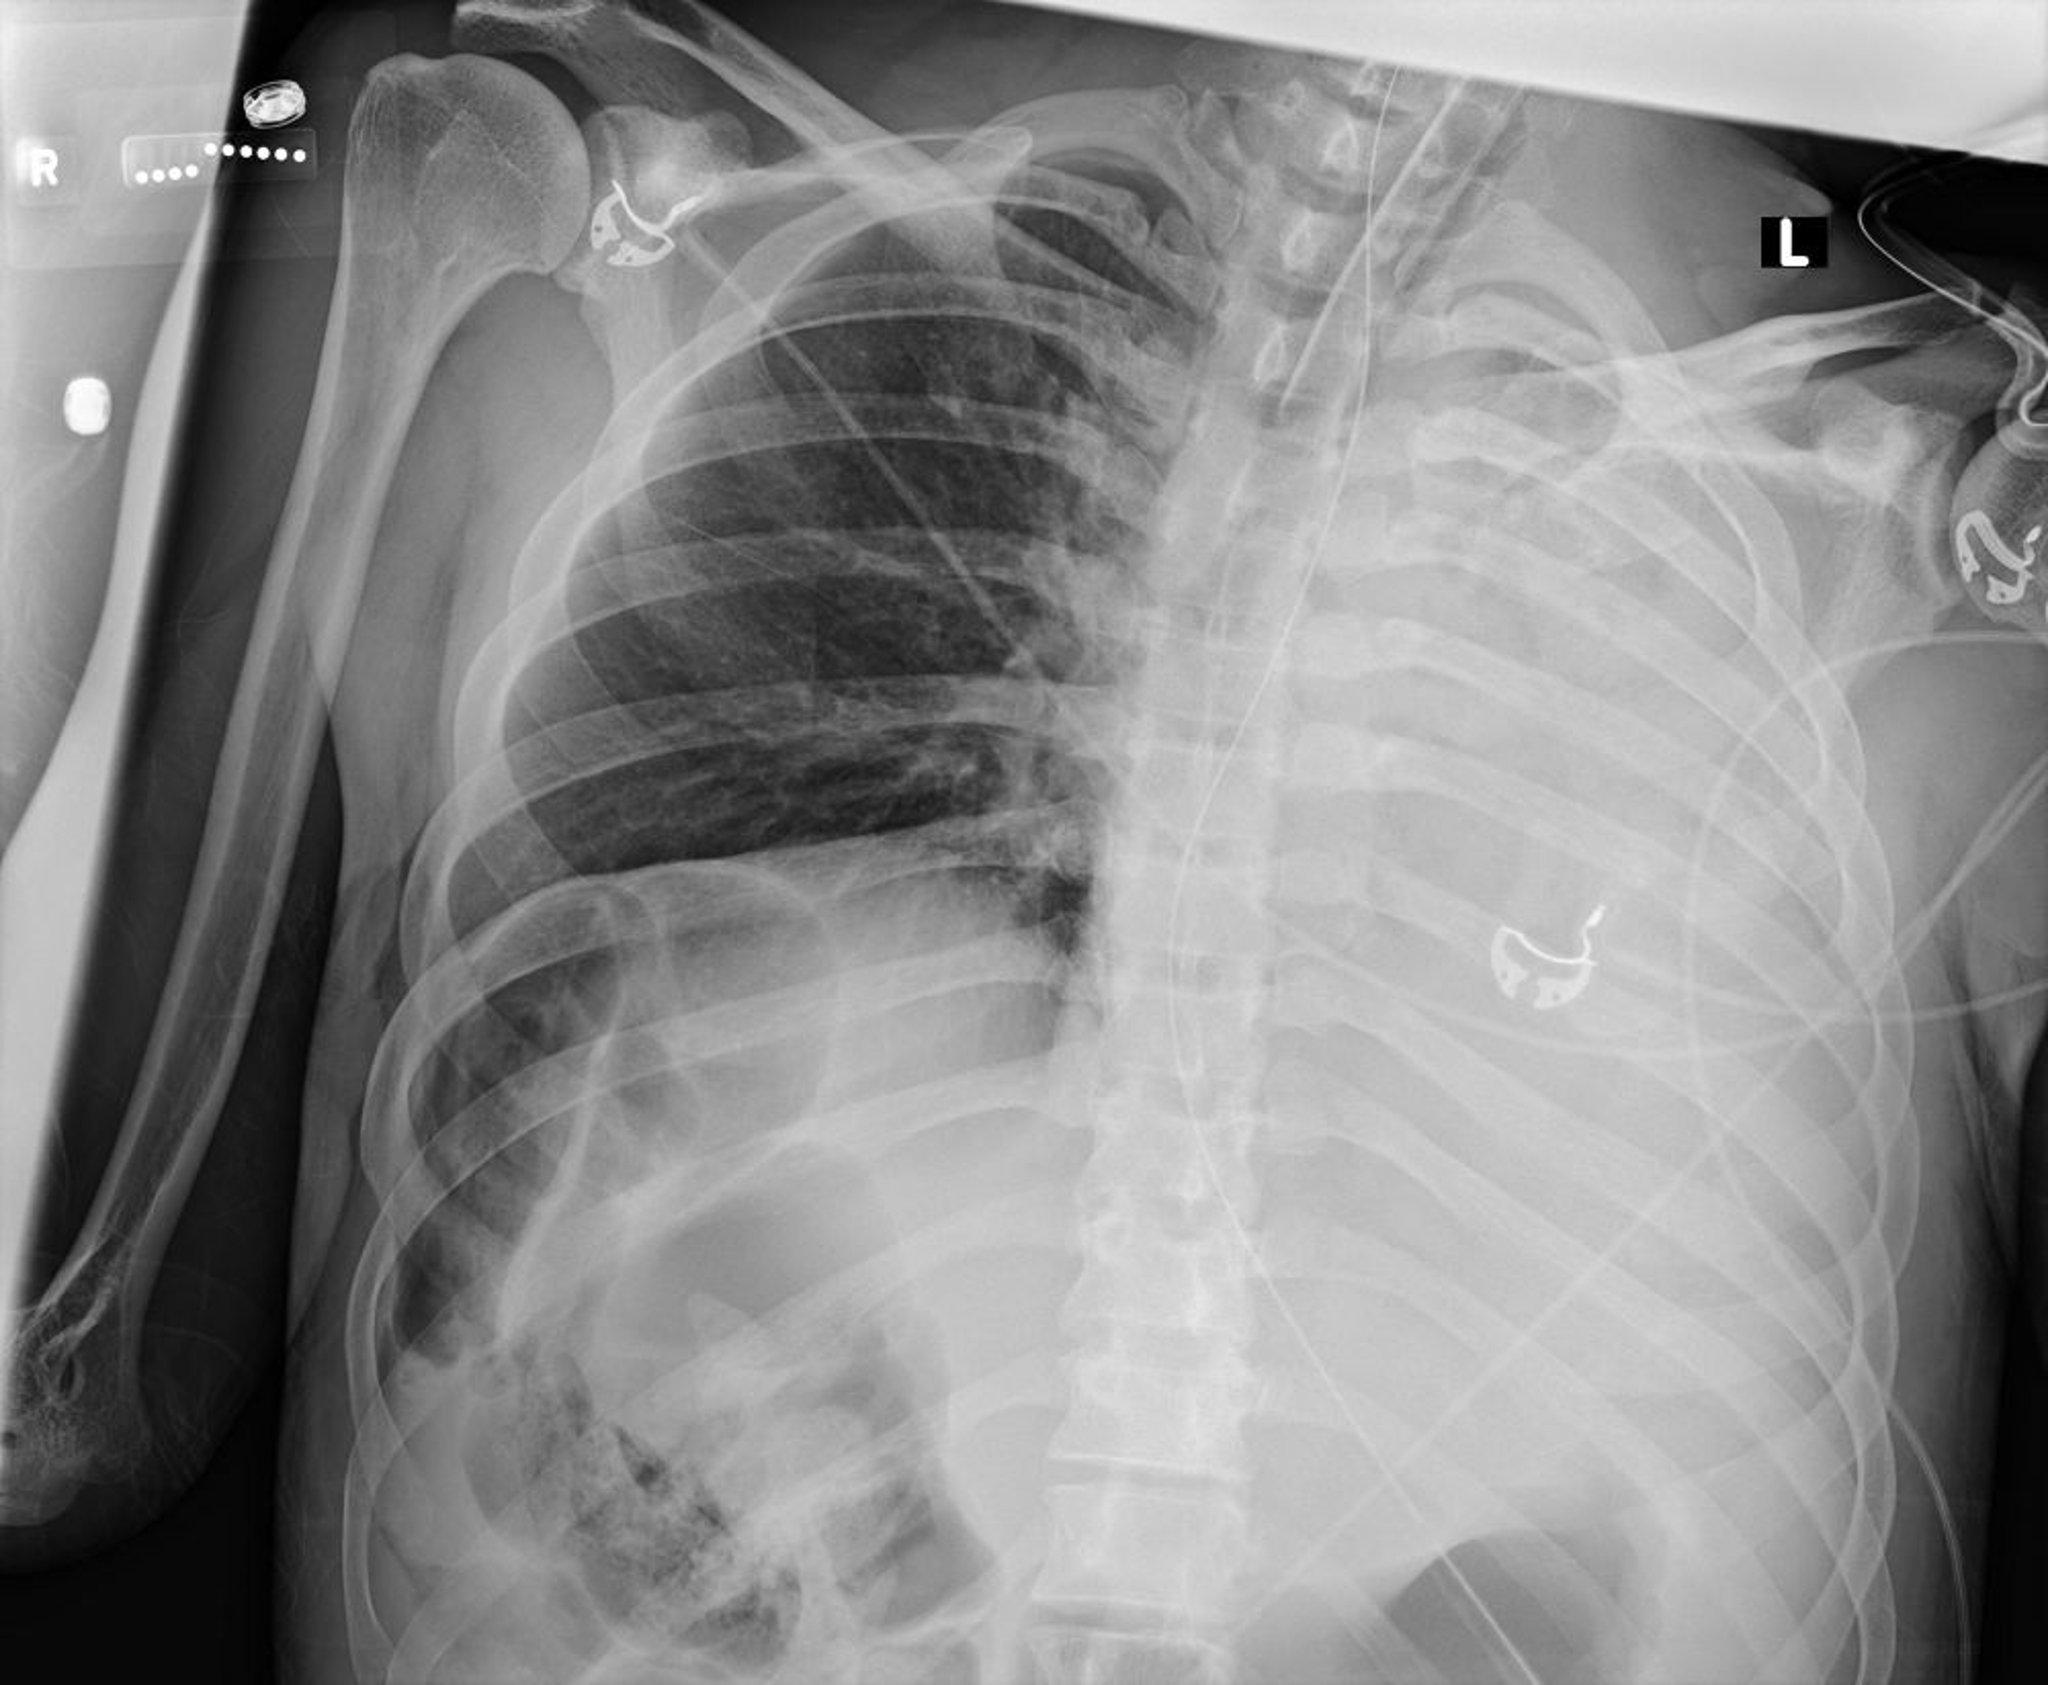

Ателектаз и Коллапс Левого Легкого (Рентген)

На данной рентгенограмме органов грудной клетки показан коллапс всех долей левого легкого вследствие слизистой пробки.

Courtesy of Alexander S. Niven, MD